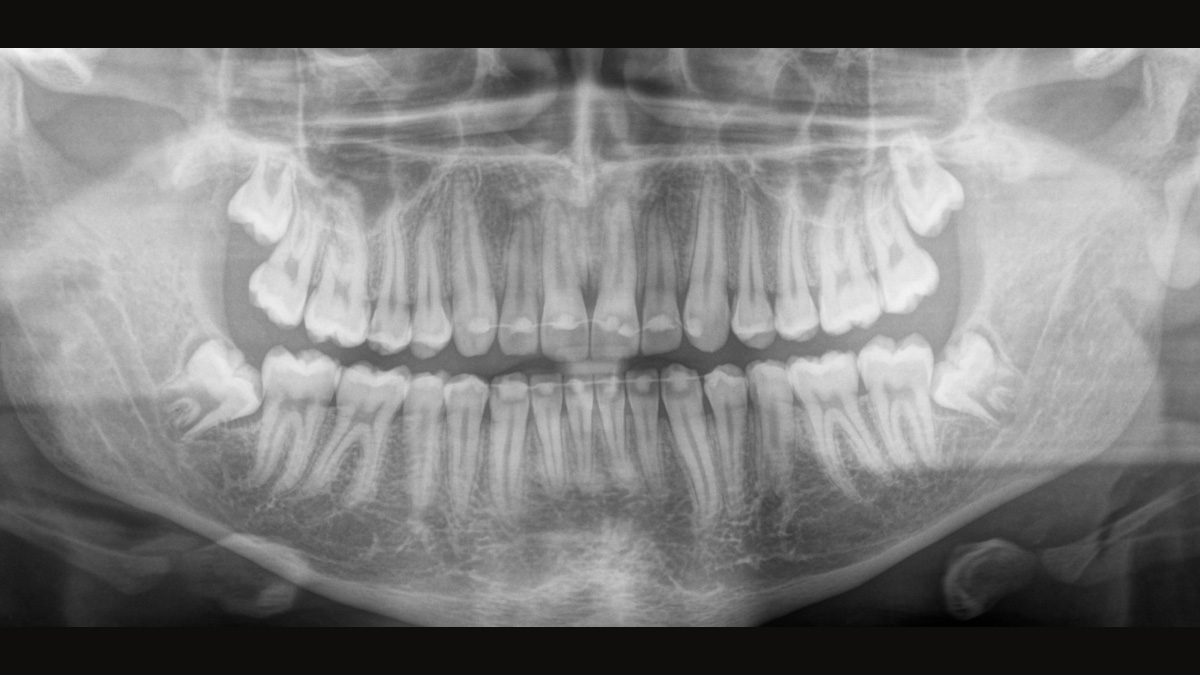

Il sensore a conversione diretta (DCS) ha rivoluzionato lo standard della radiologia panoramica. I raggi X vengono convertiti direttamente in segnali elettrici. Pertanto, non vi è alcuna perdita di segnale a causa della conversione della luce, come nel caso dei sistemi convenzionali. Il risultato: immagini con un alto livello di nitidezza e contrasto, anche a una dose di radiazioni estremamente bassa. Per informazioni diagnostiche accurate a supporto del trattamento mirato.

L’immagine seguente mostra una radiografia panoramica con e senza tecnologia DCS. Utilizzando la freccia, trascinare il controllo attraverso l’immagine per vedere la differenza che fa il sensore di conversione diretta rispetto alla qualità dell’immagine e alle possibilità diagnostiche.

La giusta messa a fuoco è fondamentale per eccellenti radiografie panoramiche. Con la funzione di autofocus si ottiene automaticamente un’immagine a fuoco con la migliore nitidezza possibile. I dispositivi radiografici Dentsply Sirona acquisiscono diverse migliaia di singole immagini in un solo ciclo e identificano automaticamente le aree in cui la mascella è posizionata in modo ottimale. Senza ulteriori passaggi manuali, queste immagini vengono quindi visualizzate in un’immagine finale nitida.

Solo alcune parti dell’immagine sono a fuoco, mentre altre aree sono sfocate.

Il sistema rileva le aree pertinenti da diverse migliaia di singole immagini in un solo ciclo e identifica automaticamente le aree in cui la mascella è posizionata in modo ottimale.

Immagini nitide.